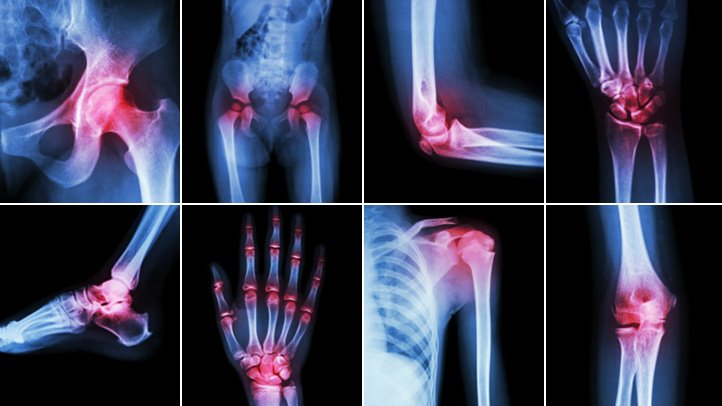

Arthritis comes in many forms. However, the most common osteoarthritis, a degenerative disease, affects the joints. As you age, the surrounding cartilage begins to wear, causing bone to bone grinding. When this happens, the affected area begins to stiffen, swell and cause you pain. As it progresses, you can lose your full range of motion and have a crippling effect wherein it can cause the area to disfigure. This is mostly present if you develop arthritis in the hands and fingers. Another common arthritis is rheumatoid. This type develops as a result of your own immune system working against you and begins to attack the joints. Since it presents many of the same symptoms as osteoarthritis, it can be hard to self-diagnose. Because there are so many different types of arthritis, seeking the assistance of a qualified professional will help to identify it correctly and then let you explore your treatment options.